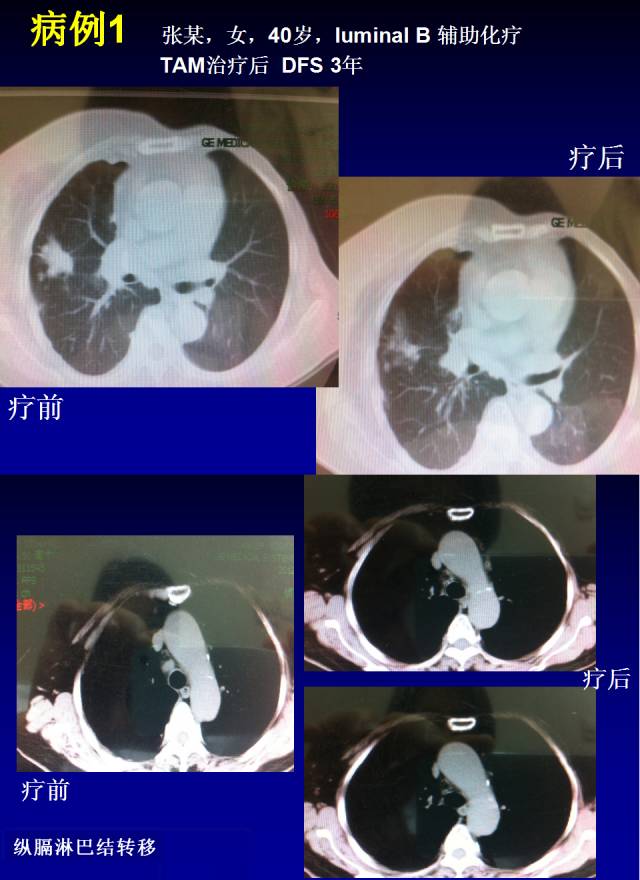

病例1:一位40岁Luminal B型患者病例,接受辅助化疗,TAM治疗3年后发现肺转移。该患者入组后接受OFS+依西美坦治疗,肺转移明显缓解,缓解时间为10个月左右。这位患者的纵隔淋巴结转移也在治疗中持续缩小(如下图)。